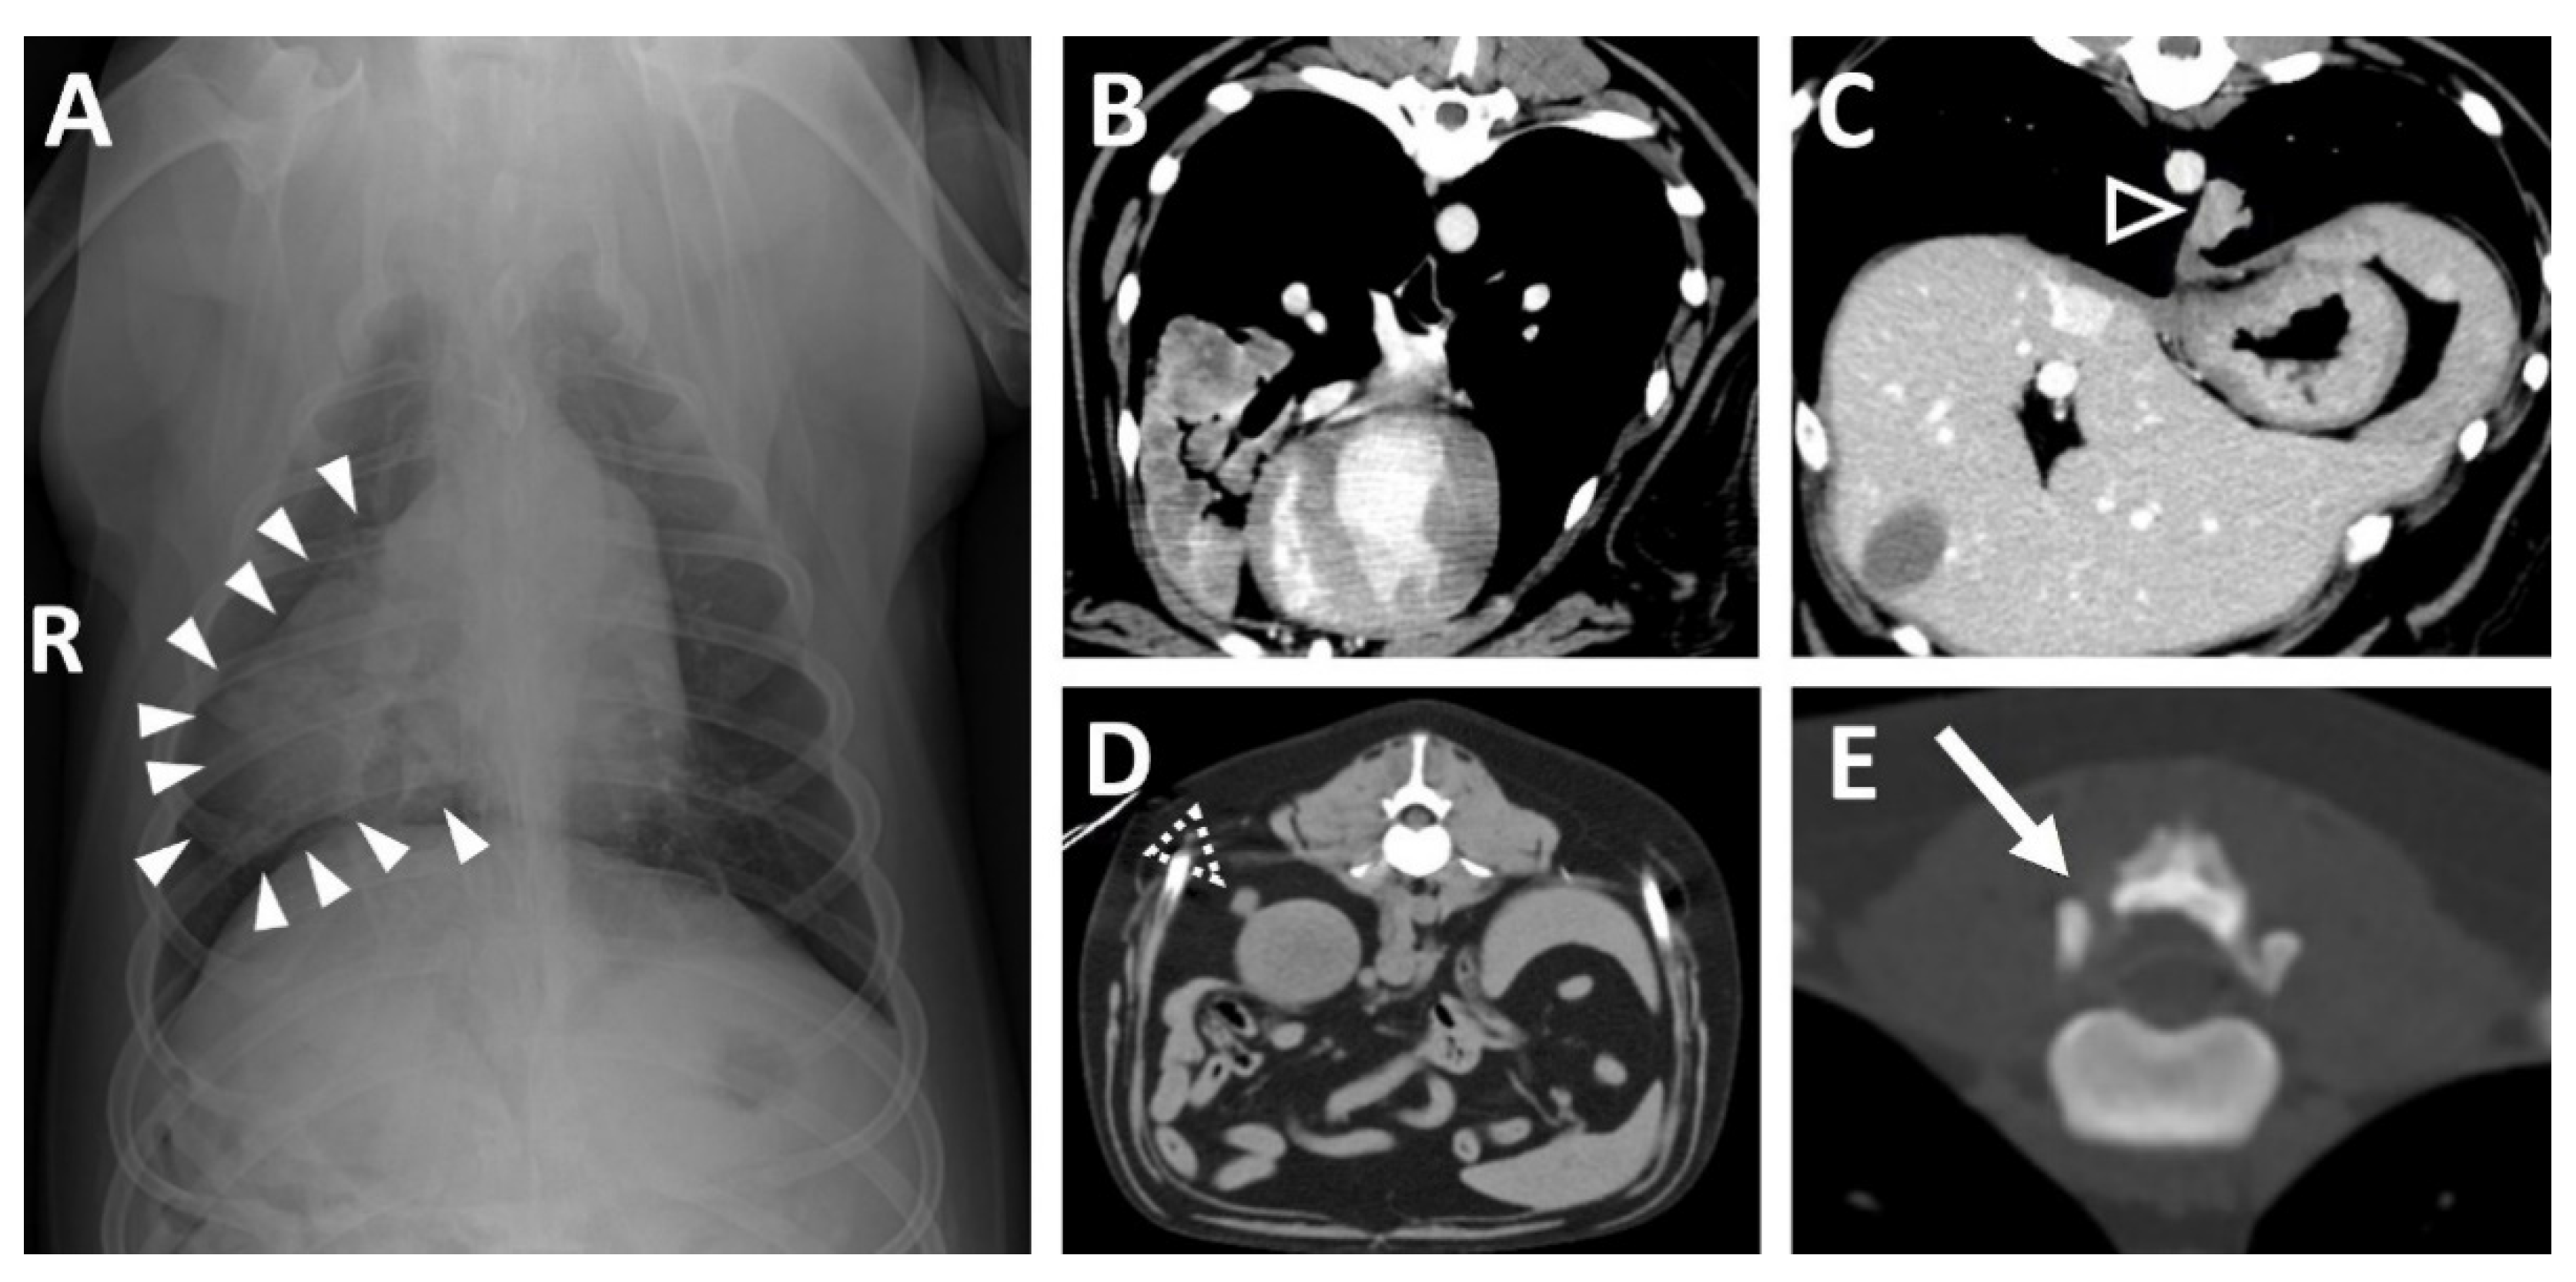

Thoracic radiography revealed a small, round soft tissue opacity in the right middle lung lobe (Figure 1A) and a lytic bone lesion adjacent to the articular facets between the thirteenth thoracic vertebra (T13) and first lumbar vertebra (L1). Abdominal ultrasonographic examination was unremarkable. Computed tomography (CT, Lightspeed, GE Healthcare, Milwaukee, WI, USA) was performed to evaluate the vertebral lesion and the mass in the lung, and CT images were obtained before and after intravenous administration of a contrast medium (Omnipaque 300; GE Healthcare, Milwaukee, WI, USA). A post-contrast CT scan revealed small soft tissue masses in the right middle lung lobe (Figure 1B) and left caudal lobe (Figure 1C). A small soft tissue mass caudal to the right kidney was also found (Figure 1D). Moreover, osteolytic changes of the vertebral lamina and pedicle of T13 were identified (Figure 1E).

Figure 1. (A Soft tissue opacity (arrowheads) in the right middle lung lobe on thoracic radiography. (B) Large mass of the right middle lung lobe and (C) small mass of the left caudal lung lobe (open arrowhead) on post-contrast transverse images. (D) Small mass (open dashed arrowhead) dorsal to the right kidney. (E) Osteolytic lesion (arrow) of the T13. (R: right, T13: the 13rd thoracic vertebra).